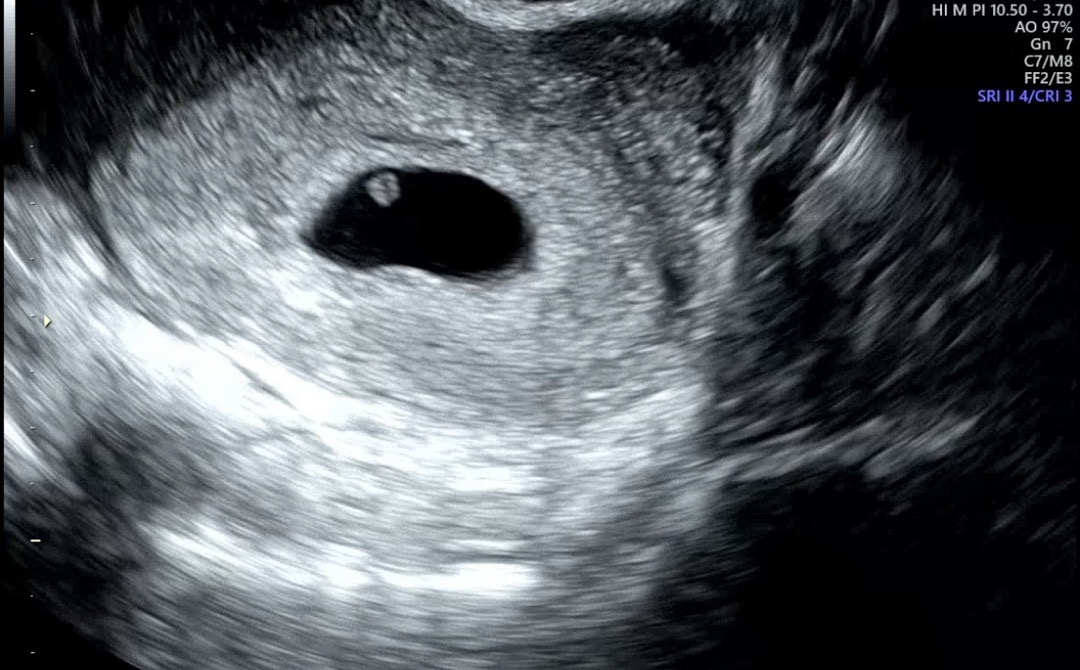

아기집과 난황은 보이는데 아기가 안보여요

막생 시점(7/4)과 관계 없이, 배란 & 착상이 모두 늦은 것 같다 하여 5주 말~6주 초로 추정하고 있는데요 (막생 기준 7주차 0일) 오늘 초음파 봤는데 아기가 안보인대요 다음주 다시 보러 가기로 했는데 그때도 안보이면 쉽지 않을 것 같다고 하시네요 ㅠㅠ (아기집 가로 2cm) 같은 경험 있으신가요..! 흑

전 시험관이긴 했지만 6주 3일에 방문했을때 아기집과 난황만 보이고 심장소리는 커녕 심장깜빡임조차 보지못했어요 ㅠㅠ 너무걱정되고 마음의 준비까지하고 7주 5일에 방문했더니 너무 예쁜 아가와 우렁찬 심장소리들었습니다!! 너무 걱정마시고 기다려보심이 좋을것 같아요!!